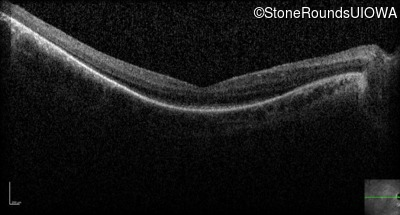

Optical Coherence Tomography - Right - 20/70 -2

Exemplar / OCT Stack

OCT Stack